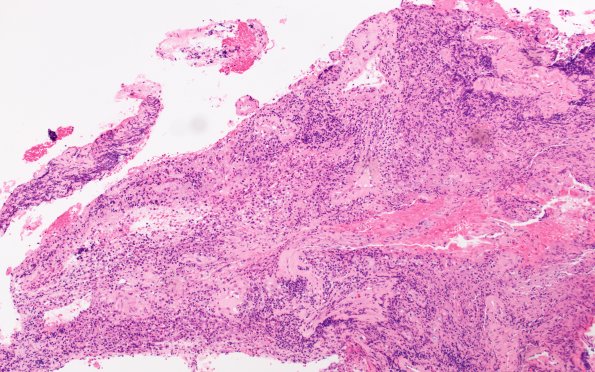

Washington University Experience | MISCELLANEOUS | Idiopathic Hypertrophic Pachymeningitis (IgG4 Disease) | 8E1 Brain (Case 8) A2 H&E 10X 1

8E1-3 The dura and leptomeninges shows a complex inflammatory infiltrate including epithelioid histiocytes, fibrosis and fibrinoid vasculitis, likely including some venous sinus elements. (H&E)